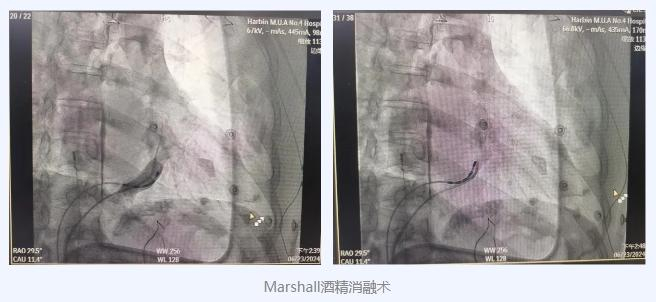

其中有两位连续性房颤患者,病史分别为2年和10年,手术前曾恒久接受药物治疗,均无法治愈和有效控制,导致患者正常生活受到极大影响,且大大增加房颤相关血栓栓塞事件的发生。电生理团队研判后决定多措并举,在传统导管消融的基础上增加Marshall静脉无水乙醇消融,以期增加房颤消融乐成率,同时制止术后产生手术相关的心房扑动。在团队精湛医术和密切配合下,历时2小时,手术圆满完成,术后患者房颤消失,恢复了梦寐以求的正常心跳。

韩颖教授介绍,近年来,随着导管消融技术及消融工具的不停进步,二尖瓣峡部线的完全阻断率已明显提高,但是仅在二尖瓣峡部心内膜面或冠状静脉窦内消融仍然难以完全阻断Marshall韧带介导的心外膜桥接传导。Marshall酒精消融术解决了导管消融“到不了”“消不到”的问题。近年来的研究显示Marshall静脉无水乙醇消融可以进一步提高二尖瓣峡部线的阻断率,可从64%提高到近100%。别的,Marshall静脉无水乙醇消融可以显著提高连续性房颤导管消融的远期乐成率。